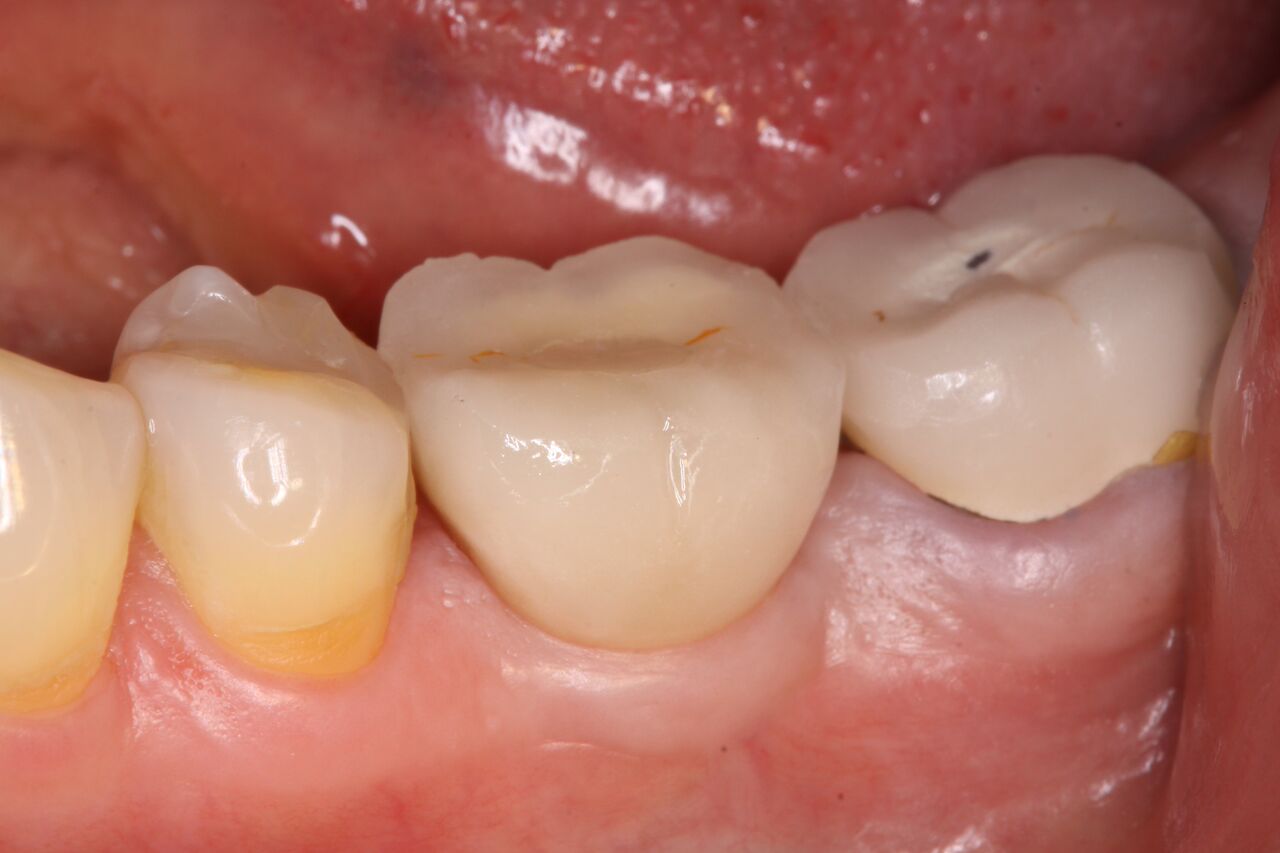

(7.) 1-year clinical postoperative of No. 19 restoration.

Figure 7

The patient was instructed in postoperative care specific to an immediately provisionally restored implant and an antibiotic and analgesic was prescribed. At 4 months, integration was confirmed. The patient was impressed for a final restoration that was cemented within 2 weeks. The final radiograph (Figure 6) and clinical photo (Figure 7) presents a 1-year postoperative demonstrating good esthetics, full bone regeneration, and a steady state of bone to the implant under loading.